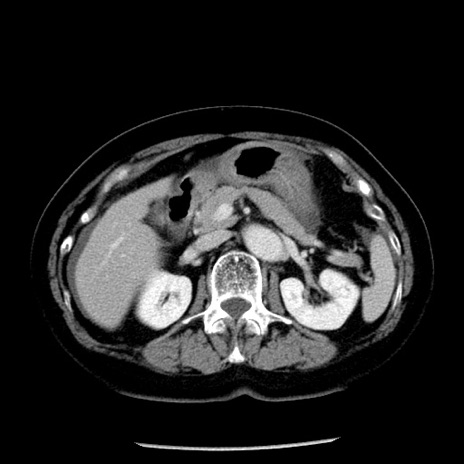

冠状断像

【症例】70歳代女性

【主訴】腹痛、嘔吐

【現病歴】15時間程前(昨晩)より腹痛あり。今朝になっても症状の改善なく、嘔吐あり。腹痛も増悪あり、救急外来受診。

【既往歴】子宮癌全摘術後

【身体所見】意識清明、BP 121/72mmHg、P 74bpm、SpO2 100%(RA)、腹部:平坦・軟、腸雑音ほぼ聴取せず。下腹部・心窩部・臍左上に圧痛あり。反跳痛なし。

【データ】WBC 10600、CRP 0.15